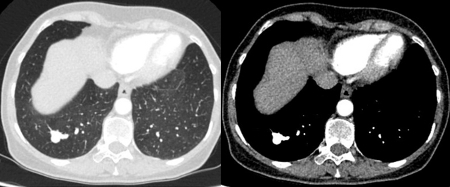

Tomografia computadorizada (TC) mostrando exemplos de nódulos perifissurais malignos. Observe a borda espiculada dos nódulos e a evidente retração da fissura adjacente. Ambas as análises de tecido de ressecção confirmaram adenocarcinoma de pulmão

Do acervo de Dr. George Tsaknis, MD, PhD, FRCP (Londres), MRQA, MAcadMEd, PGCert; usado com permissão